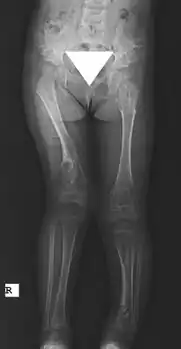

X-ray hips and legs: multiple enchondroma

X-ray legs: Ollier disease